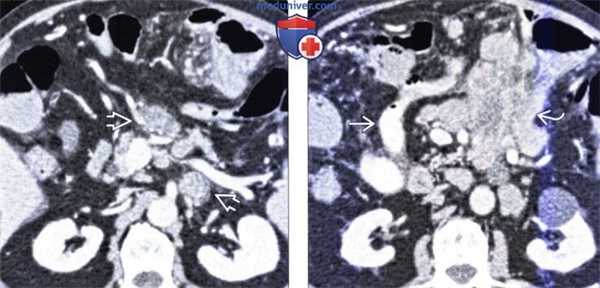

(Слева) Еюногастральная инвагинация как осложнение резекции желудка и создания анастомоза по Бильрот 2. На КТ определяется петля тощей кишки с толстой стенкой и признаками ишемии, находящаяся внутри растянутой культи желудка.

(Справа) На корональной КТ с контрастным усилением у этого же пациента определяется ретроградная инвагинация с внедрением кишки, жировой клетчатки брыжейки и сосудов в культю желудка. Это достаточно редкое осложнение, которое, тем не менее, может привести к кишечной обструкции и ишемии.

(Слева) На рентгенограмме в прямой проекции (не представлена) у пожилой пациентки было выявлено выпадение желудка в грудную полость (околопищеводная грыжа четвертого типа). На КТ определяется, что пищеводно-желудочный переход, а также пилорический отдел желудка находятся в грудной полости.

(Справа) На более каудальном КТ срезе у этой же пациентки визуализируется околопищеводная грыжа четвертого типа. Дно желудка располагается ниже антрального и пилорического отдела. В этом случае можно говорить об органоаксиальном «положении» желудка в противовес «завороту»; обструкции не возникает. (Слева) На аксиальной КТ без контрастного усиления у женщины 63 лет, страдающей от перемежающейся боли в грудной клетки и животе, определяется, что желудок целиком находится в грудной полости (околопищеводная грыжа четвертого типа). Обратите внимание на большое количество контраста, оставшегося в желудке спустя два часа после его приема.

(Справа) На аксиальной нативной КТ у этой же пациентки также визуализируется желудок в грудной полости с наличием контрастного вещества, задержавшегося в его просвете. (Слева) На корональной нативной КТ у этой же пациентки лучше определяется заворот желудка, при котором большая и малая кривизна меняются местами.

(Справа) На корональной КТ без контрастного усиления у этой же пациентки визуализируется контрастное вещество, задержавшееся в среднем отделе грудного сегмента пищевода. У пациентки наблюдалась, как минимум, частичная обструкция; ей было выполнено оперативное вмешательство, при котором подтвердился органоаксиальный заворот.